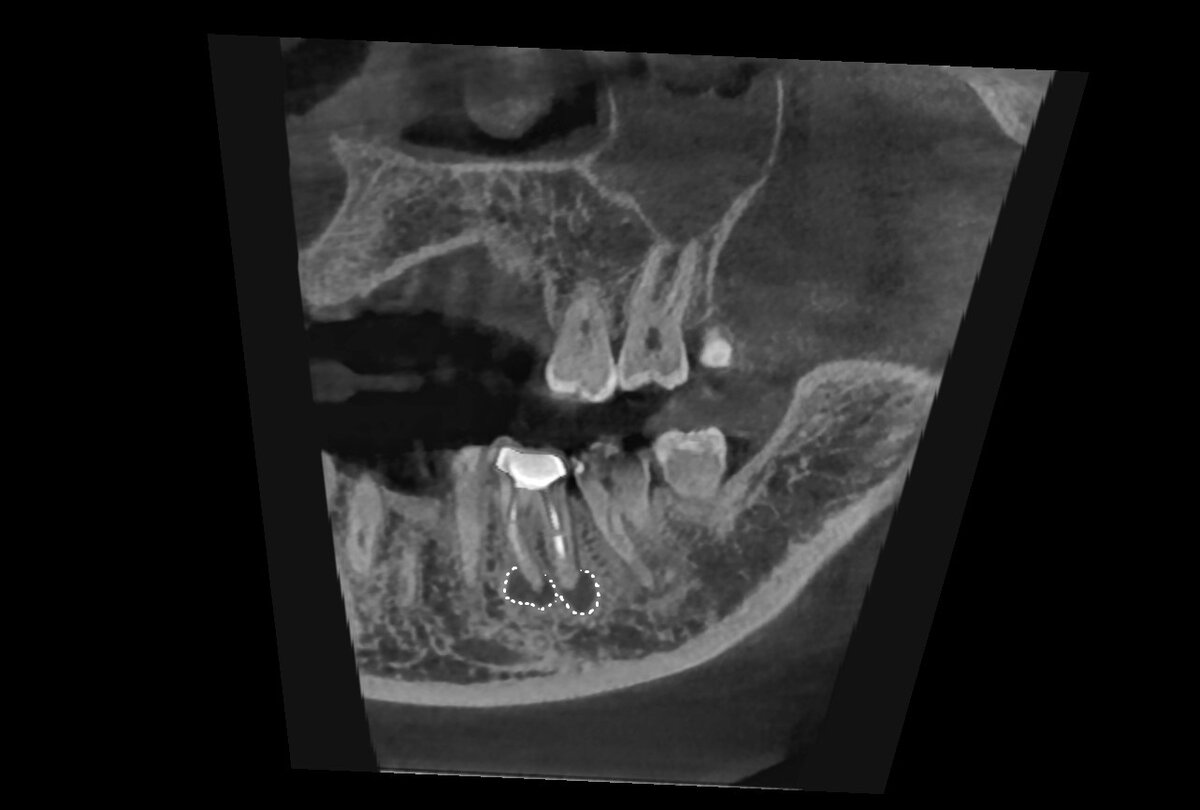

Исходная ситуация. Зуб 36 под коронкой, лечен когда - то давно. И случайно на кт исследовании обнаружен очаг просветления костной ткани в проекции верхушек корней (так нужно обычно описывать то, что мы видим на рентген снимке). На обывательском языке «киста на зубе том». В общем инфекционный хронический процесс, который потенциально мог начать беспокоить пациента в самый неподходящий момент жизни. Подробнее об этом заболевании читайте здесь (отдельная статья с очень хорошей обратной связью) ->

Ситуация до:

в области верхушек корней

очаг хронической инфекции обведен белыми точками